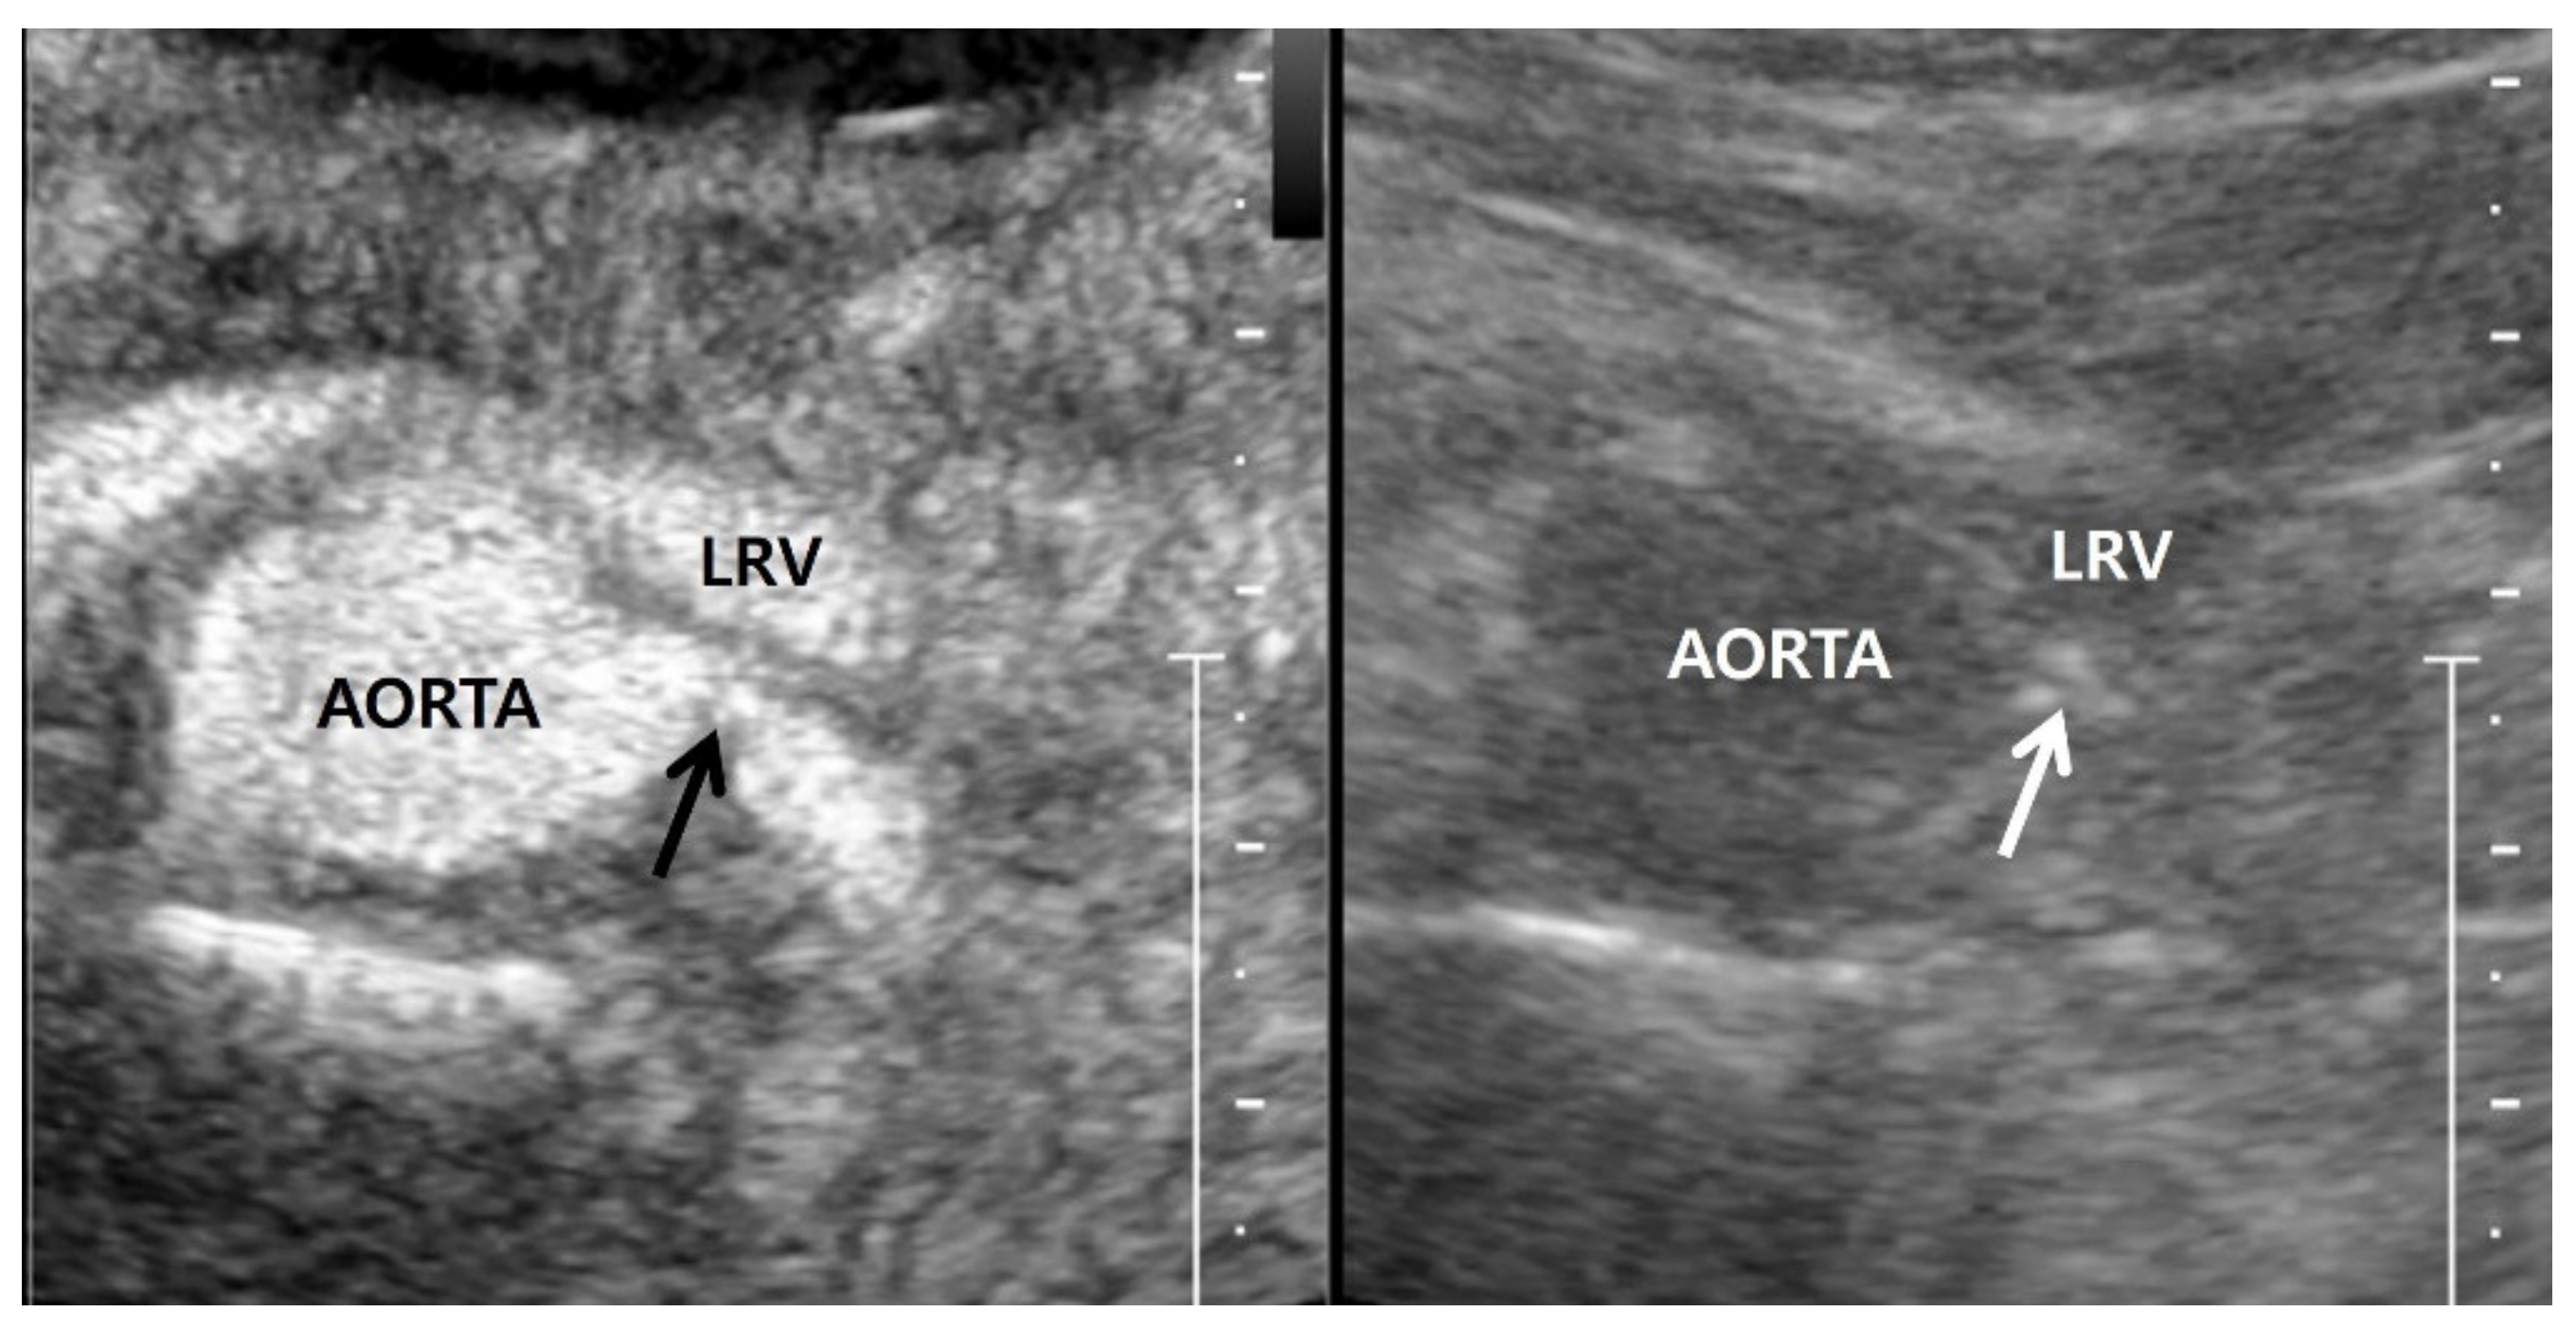

Renal artery US is not established terminology on PubMed; there are no papers defining it, even though many investigations have demonstrated the utility of US in assessing the velocity of bilateral renal arteries. It can be defined as an US technique used to directly assess the renal artery. The renal artery is not easy to detect with US because it is a deeply situated small vessel [23]. The right and left renal arteries are sited posterior to the left renal vein. Therefore, to assess RAS, the first step is to find the left renal vein [44]. The right renal artery arises from 9–12 o’clock of the aorta and passes behind the inferior vena cava (Figure 1). These anatomical characteristics result in the focal angulation of the right renal artery, in which blood flow is clearly visible because of the good frequency shift. In contrast, the left renal artery arises from 2–5 o’clock of the aorta and travels away from the transducer (Figure 1). For these reasons, the frequency shifts of the left renal artery are weaker than those of the right renal artery, so the left RAS is more difficult to detect than the right RAS with gray-scale, Doppler, and contrast-enhanced US. However, US has difficulties in detecting RAS in the aberrant renal artery, accessary renal artery, and polar branches.

Figure 1.

Normal anatomy of renal artery. (a) Gray-scale US axial image shows right renal artery (arrows) arising 10 o’clock from the aorta. It shows a short segmental angulation behind the inferior vena cava (IVC); (b) gray-scale US axial image shows left renal artery arising 4 o’clock from the aorta. It is located below the left renal vein (LRV) and is traveling away from the transducer without angulation.